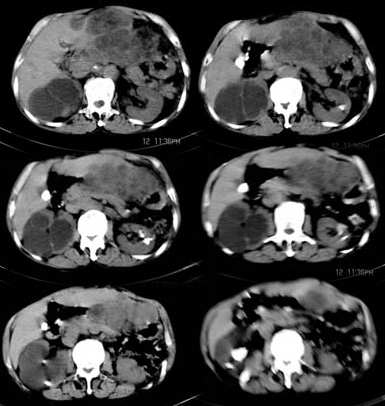

标题: CT2840:腹部占位,请会诊? [打印本页]

标题: CT2840:腹部占位,请会诊?

男,66岁,上腹部胀疼,无其他不适.

1胆管细胞癌

2右肾囊肿

考虑胆管细胞型肝癌可能性大,右肾囊肿,左肾结石

考虑胆管细胞型肝癌可能性大,胆结石,双肾结石。肝、肾血管平滑肌脂肪瘤不除外。

双肾结石,胆结石,肝内胆管扩张,肝左叶占位病变,请做增强ct.

考虑肝、肾血管平滑肌脂肪瘤可能,肾结石,右肾积水。

肝胆管细胞癌,右肾积水

考虑胆管细胞型肝癌可能性大,胆结石,双肾结石。右肾积水。 建议增强扫描及复部肠道准备

肝左叶胆管细胞癌,胆囊结石,双肾结石,右肾积水。

胃肠道恶性肿瘤伴肝脏转移,腹膜转移。

右肾结石,囊肿。

肾脏的结石中肾盂叫结石,在肾实质叫钙化。肝左叶胆管细胞癌可能,钙胆汁,右肾结石,左肾实质钙化